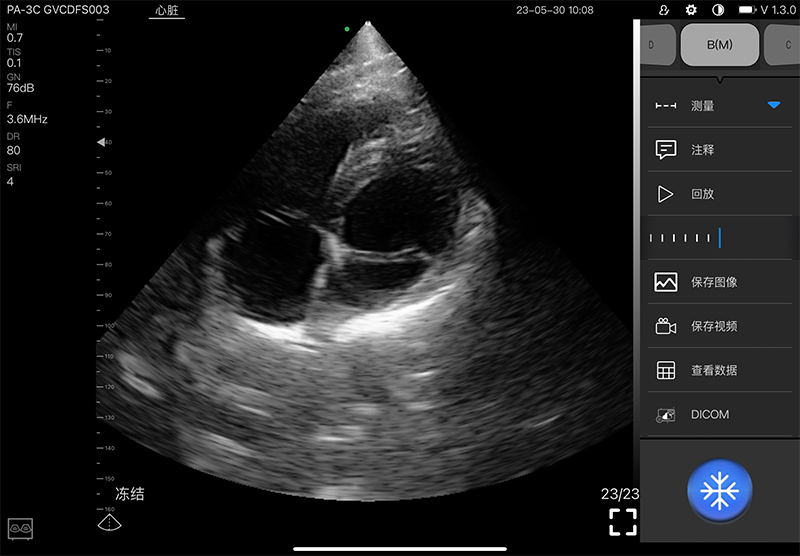

- Scanning mode: Electronic phased array

- Elements: 128

- Channel: 32

- Display mode: B, B/M, and Color, PW, CW, PDI

- Frequency: central 2.8MHz, cardiac reverse harmonic

3.6mhz, and the transcranial fundamental 2.2MHz

- Display Angle: 80°

- Display Depth: 90/160/200/240mm

- Image Adjust: Gain, DYN, Focus, Depth, Harmonic, Denoise

- Noise reduction: 0-1-2-3-4

- Gain: 30db-105db

- Dynamic Range: 40/50/60/70/80/90/100/110

- Measure: Length, Area, Angle, Heart

- Image frame rate: 15~20 framescond